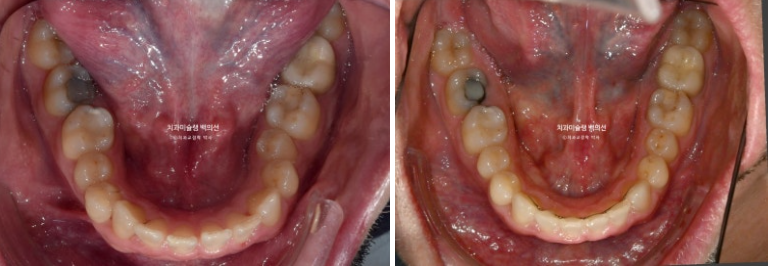

23.01~25.09

사랑니까지 잘 배열이 되었습니다.